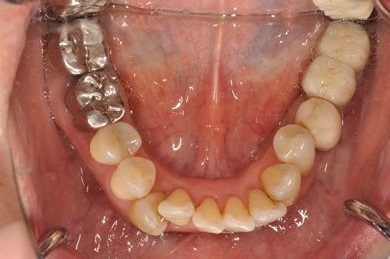

インプラントの症例写真 IMPLANT

インプラント治療+ソケットリフト+GBR

| 性別/年齢 | 女性 / 55歳 | ||||||||||||||||||||||||||||||||

| 主訴 | 奥歯が3本抜歯されてしまったあとにインプラントを入れたい。 | ||||||||||||||||||||||||||||||||

| 治療内容 | インプラント3本(ソケットリフト、GBR)、ハイブリッドセラミック3本 | ||||||||||||||||||||||||||||||||

| 総治療費 | 1,295,300円 | ||||||||||||||||||||||||||||||||

| 治療期間 | 8ヶ月 |